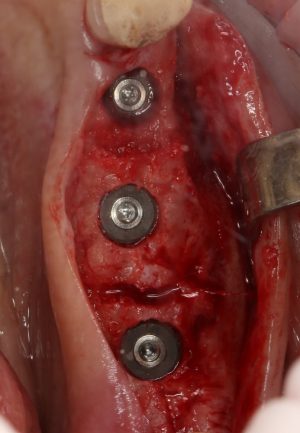

Рекомендации по установке имплантов. Для всех. Часть III